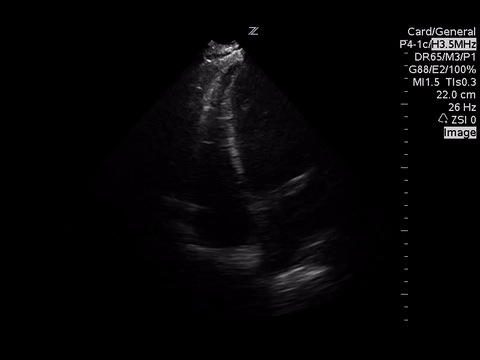

A focused echocardiogram was performed to try to differentiate between these causes. These are the images obtained:

| Apical 4 Chamber View |

Based on the A4C view, the RV appears smaller than the LV and appears to be contacting well, so there are no echo signs of RV strain.

A subxyphoid view is usually the most sensitive for looking for an effusion, but based on the views obtained there’s no effusion seen.